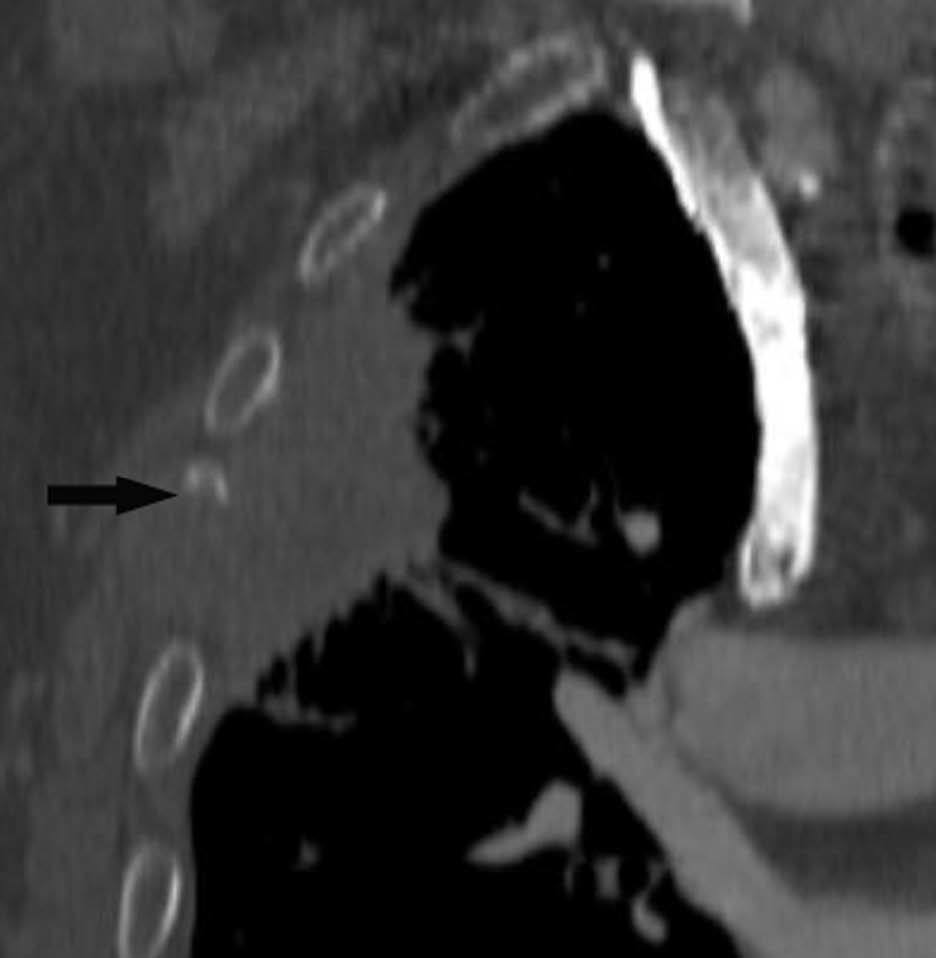

Fig. 2.--T4. (A) Corte axial de tomografía computarizada (TC) torácica con contraste. Tumor hiliar derecho que infiltra la arteria pulmonar derecha, la vena cava superior y engloba al bronquio intermediario. (B) Reconstrucción coronal oblicua, longitudinal al eje de la arteria pulmonar derecha, que muestra cómo engloba el tumor a la rama del truncus superior (flecha blanca) e inferior (flecha negra).